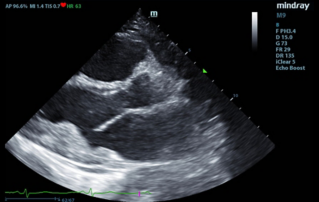

Ultrasound Journal 34 - Use of IOTA-ADNEX & O-RADS risk assessment models in MDT management of Adult Granulosa Cell Tumor

Comprehensive overview of granulosa theca cell tumors of the ovary, covering epidemiology, clinical presentation, diagnosis, treatment options, and prognosis for both adult and juvenile types.